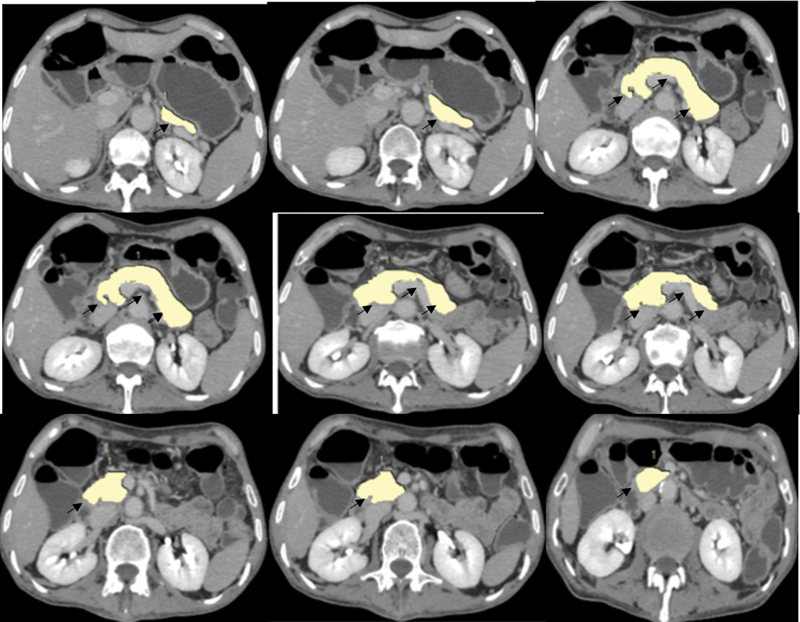

Background  The most crucial step in the management of type 2 diabetes is identifying its pathogenesis and progression. Fat accumulation in the pancreas and decreased parenchymal volume can influence pancreatic function due to insulin resistance or β-cell dysfunction. This study aims to find out the difference in pancreatic volume and fat content by using contrast-enhanced computed tomography (CECT) between normal subjects and patients with different durations of type 2 diabetes mellitus (T2DM). Methods  This was a cross-sectional study. Patients who underwent CECT abdomen for the evaluation of conditions other than pancreatic origin were included. The study group was divided into three subgroups according to the duration of diabetes as <5 years, 5 to 10 years, and >10 years. In total, 40 nondiabetic controls were included. Pancreatic fat volume and parenchymal volume were measured in cm 3 using CECT. Correlation between pancreatic parenchymal and fat volume with the duration of T2DM as well as with levels of hemoglobin A1c, random blood sugar, serum triglyceride, low-density lipoproteins, and high-density lipoproteins was done. Results  T2DM patients had significantly ( p  < 0.001) lower pancreatic parenchymal volume (mean value of 57.08 ± 8.26 cm 3 in diabetics and 72.23 ± 3.41 cm 3 in controls) and higher pancreatic fat volume (mean value of 3.08 ± 1.90 cm 3 in diabetics and 0.67 ± 0.27cm 3 in controls) as compared to nondiabetic controls. In patients with T2DM, as the duration of T2DM increased, pancreatic parenchymal volume decreased and pancreatic fat volume increased. Conclusion  Reduction in pancreatic volume and fat deposition may have a role in the onset and progression of diabetes. Determining the pancreatic volume and fat content would be useful for identifying high-risk patients and determining the pathogenesis of the development of diabetes.

Abstract Image